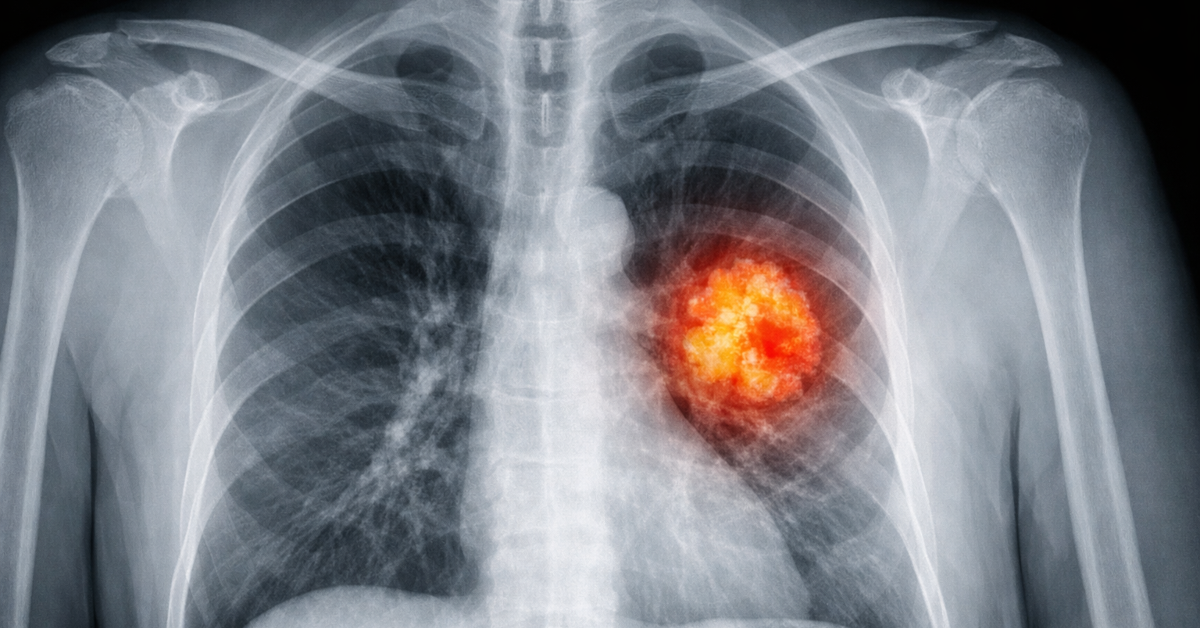

Rakovina plic - jak se pozná a proč nepodceňovat prevenci ani v mladším věku

Rakovina plic patří mezi závažná onkologická onemocnění především proto, že v počátku nemusí vyvolávat jednoznačné příznaky. Některé změny se rozvíjejí pomalu a člověk si je vysvětluje únavou, stresem, věkem nebo prodělanou infekcí.

Když se lidé ptají, jak se pozná rakovina, často čekají jeden typický příznak. Ve skutečnosti je situace složitější. U rakoviny plic bývají první projevy nenápadné a samy o sobě nemusí znamenat nádorové onemocnění. Důležité je spíše to, zda jsou nové, přetrvávají, opakují se nebo se postupně zhoršují.